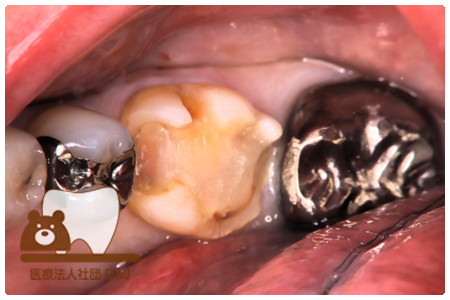

症例7フルジルコニアクラウン

治療前

治療後

43歳 女性

- 治療内容

- 虫歯で大きく失われた歯に対して、土台としてファイバーコアを使用し、その上にフルジルコニア製の被せ物を装着しました。見た目と強度を両立した自由診療の治療です。

- 治療期間

- 5カ月

- 費用

- 自費

フルジルコニアクラウン:77,000円(税込)(R7.12月現在)

- その他の治療の費用は含まれておりません。

- リスク・副作用

- 硬い素材のため、かみ合う歯に負担がかかることがあります。将来取り外す場合に歯に負担がかかることがあります。強い力が加わると、まれに欠けたり割れたりすることがあります。